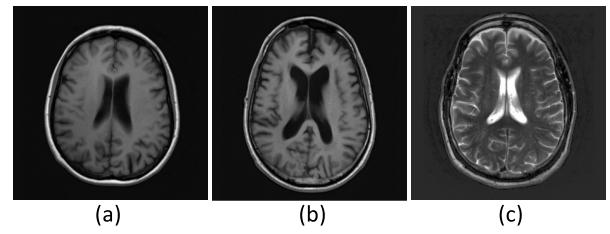

Fig. 6. Contrast visualization examples of in-distribution and out-ofdistribution data. (a) and (b): T1-weighted image; ©: T2-weighted image.

图6 分布内数据与分布外数据的对比可视化示例 (a)、(b)为T1加权图像;(c)为T2加权图像。